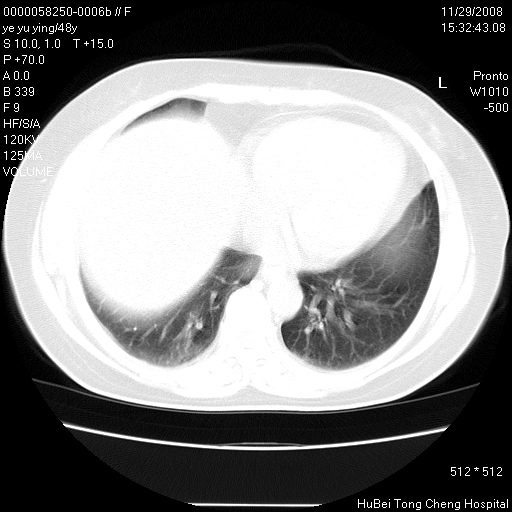

以下是引用zsl6918在2008-11-29 21:47:00的发言:[br]恶性肿瘤病史,转移瘤首先考虑。脂肪肝,胆囊结石。

以下是引用huenhao在2008-11-29 22:11:00的发言:[br]脂肪肝,胆囊结石。左肺病灶建议定期复查。

以下是引用liuyue在2008-11-30 5:44:00的发言:[br]1.左肺病变,首先考虑感染性病变,转移待排;建议治疗后复查。[br]2.肝脏密度普遍减低,考虑与化疗有关。[br]3.胆囊结石.